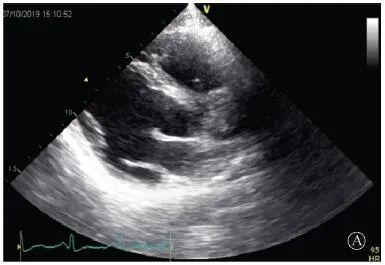

A:胸骨旁长轴平面,左室舒张末内径略增大,室壁无明显增厚;

B:胸骨旁左室短轴切面心尖水平,可见心肌肌小梁增多,其内可见隐窝(箭头所示)

图3 患者入院后超声心动图